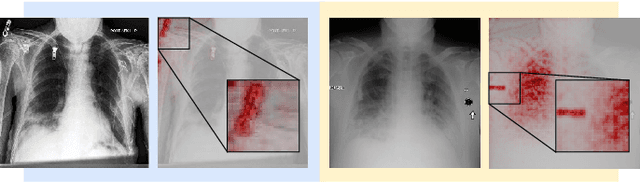

Abstract:The recent trend of integrating multi-source Chest X-Ray datasets to improve automated diagnostics raises concerns that models learn to exploit source-specific correlations to improve performance by recognizing the source domain of an image rather than the medical pathology. We hypothesize that this effect is enforced by and leverages label-imbalance across the source domains, i.e, prevalence of a disease corresponding to a source. Therefore, in this work, we perform a thorough study of the effect of label-imbalance in multi-source training for the task of pneumonia detection on the widely used ChestX-ray14 and CheXpert datasets. The results highlight and stress the importance of using more faithful and transparent self-explaining models for automated diagnosis, thus enabling the inherent detection of spurious learning. They further illustrate that this undesirable effect of learning spurious correlations can be reduced considerably when ensuring label-balanced source domain datasets.

Abstract:Current machine learning models have shown high efficiency in solving a wide variety of real-world problems. However, their black box character poses a major challenge for the understanding and traceability of the underlying decision-making strategies. As a remedy, many post-hoc explanation and self-explanatory methods have been developed to interpret the models' behavior. These methods, in addition, enable the identification of artifacts that can be learned by the model as class-relevant features. In this work, we provide a detailed case study of the self-explaining network, ProtoPNet, in the presence of a spectrum of artifacts. Accordingly, we identify the main drawbacks of ProtoPNet, especially, its coarse and spatially imprecise explanations. We address these limitations by introducing Prototypical Relevance Propagation (PRP), a novel method for generating more precise model-aware explanations. Furthermore, in order to obtain a clean dataset, we propose to use multi-view clustering strategies for segregating the artifact images using the PRP explanations, thereby suppressing the potential artifact learning in the models.